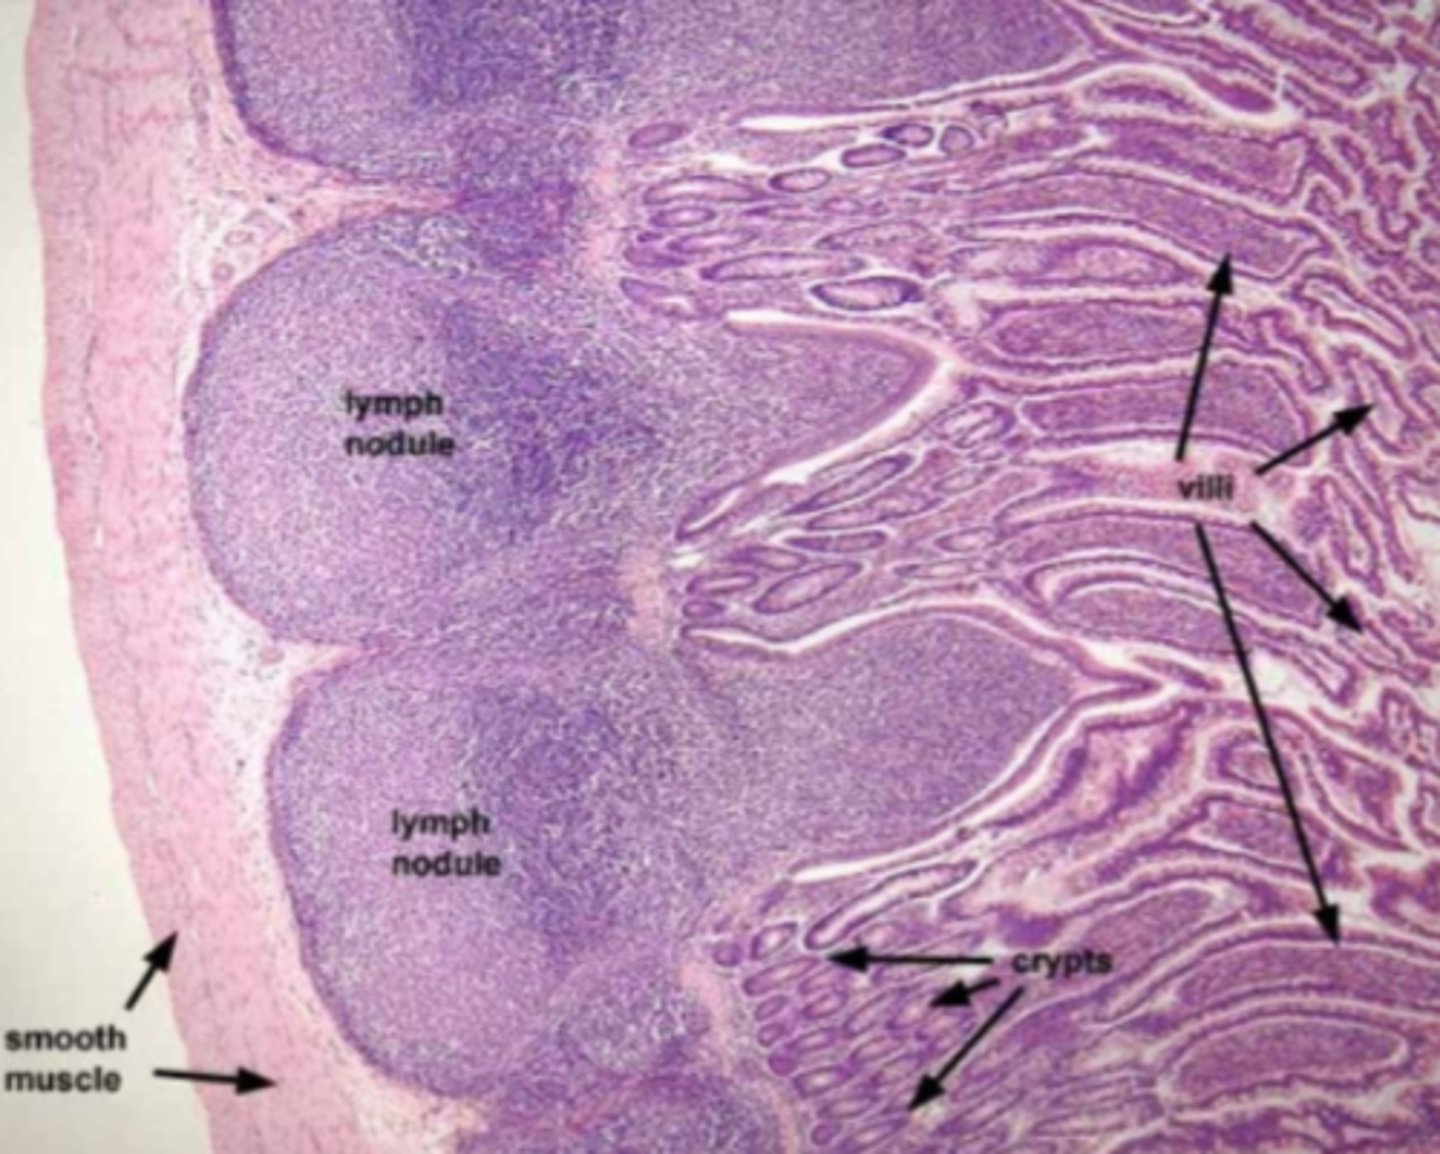

ileum

What is this?

ileum Peyer's patch

What is this?

duodenum

What is this?

Brunner's glands

What are the glands in the duodenum?

jejunum

What is this?

Jejunum has no Brunner's gland or malt tissue

duodenum and ileum vs jejunum